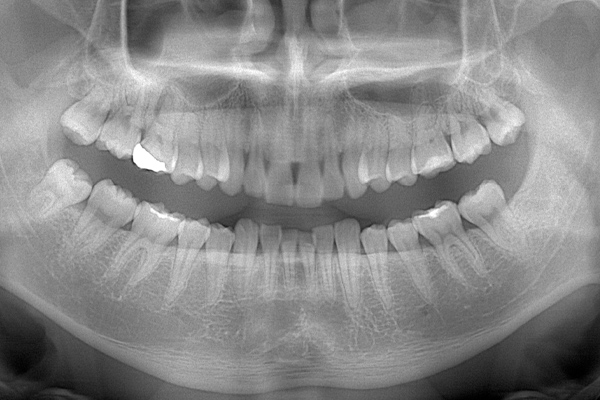

こちらは数年前の私のレントゲン写真です。右上の親知らずが斜めにはえています。お口の中には歯の頭の1部分が見えている状態です。

時々歯茎が腫れて痛かったので、抜いてもらうことにしました。親知らずが上顎洞と接していたため、抜歯後に上顎洞と口腔内が交通しましたが、2週間ほどで塞がりま

ます。

上顎はしっかり親知らずがはえています。下顎は右(青)はしっかりはえていますが、虫歯になっています。下顎の左(赤)は斜めにはえています。またこちらも虫歯になっています。

検査時のレントゲン写真です。